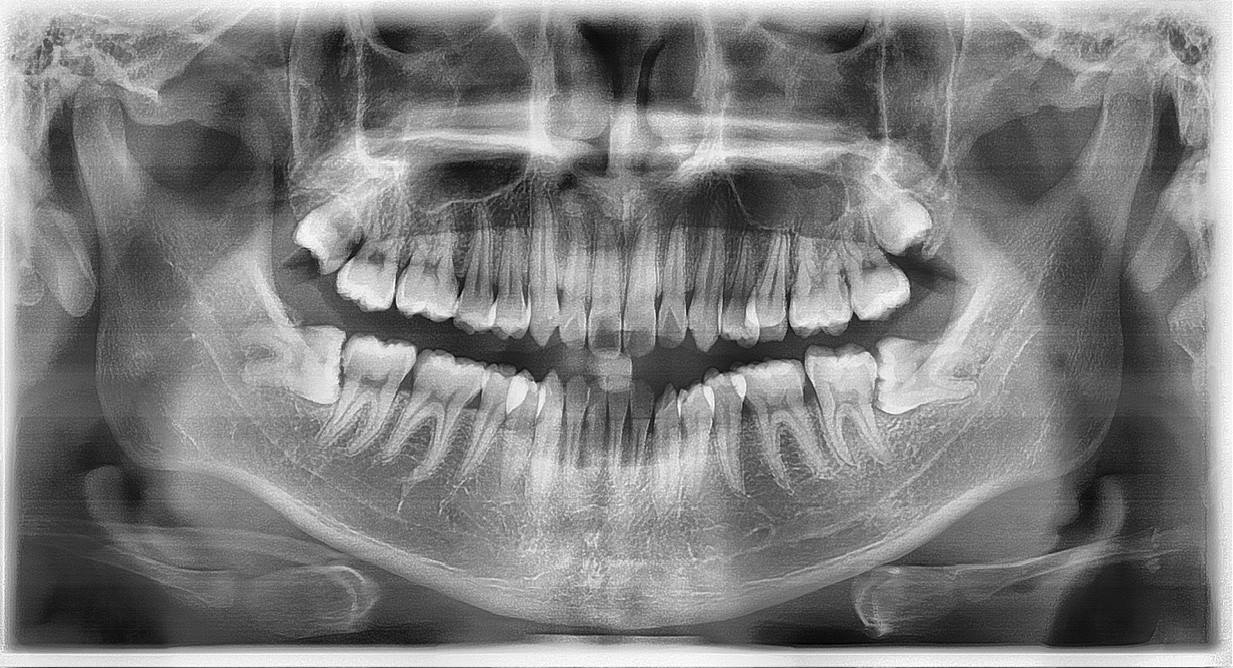

Tại khoa Răng Hàm Mặt Bệnh viện Bưu điện, quy trình nhổ răng khôn được thực hiện theo phác đồ khoa học đảm bảo an toàn cho người bệnh. Bác sĩ sẽ thăm khám lâm sàng và yêu cầu chụp X-quang để đánh giá chính xác vị trí, hướng mọc cũng như mức độ ảnh hưởng của răng khôn đối với các cấu trúc xung quanh. Dựa trên kết quả này, bác sĩ sẽ đưa ra phương án điều trị phù hợp giúp hạn chế tối đa sang chấn trong quá trình nhổ răng.